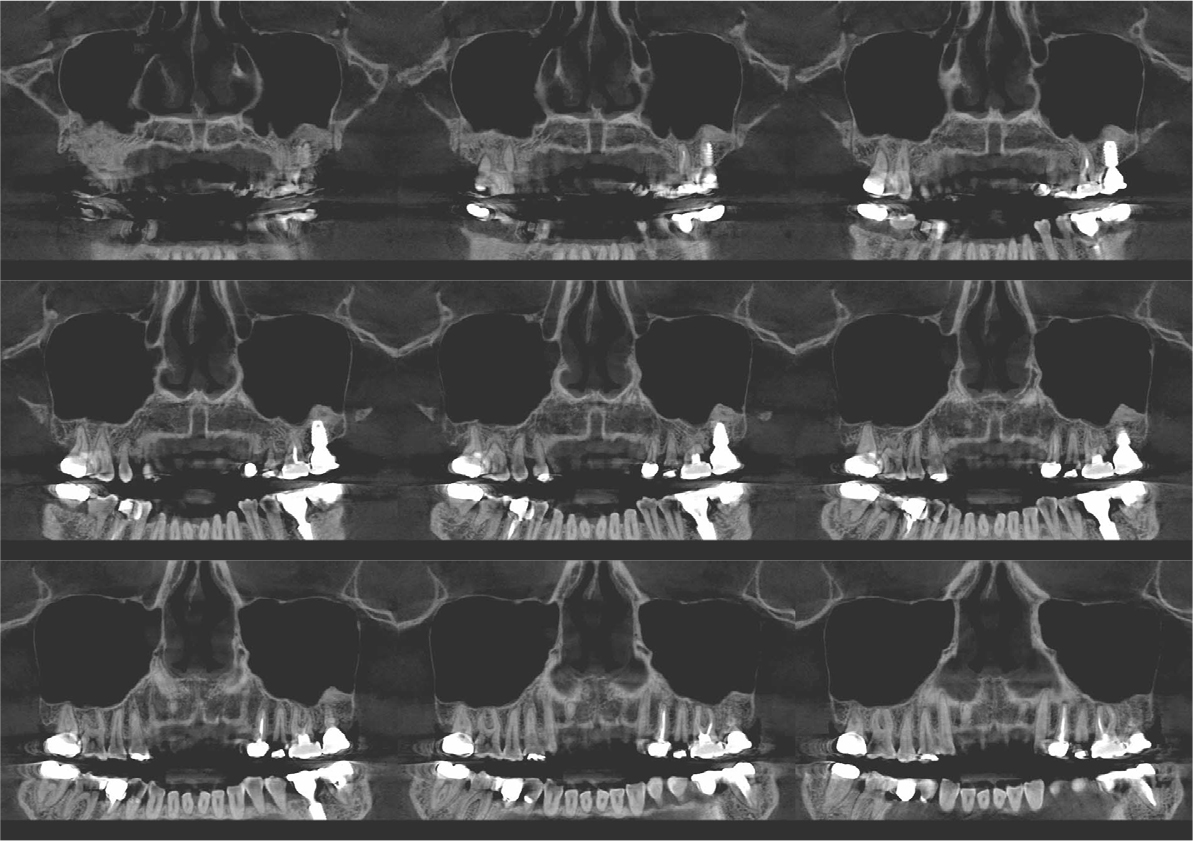

An implant with 5.0 mm diameter and 8.0 mm length (Superline; Dentium, Seoul, Korea) was placed with 0.5 cc of eproteinized bovine bone mineral (DBBM; Bio-Oss®, Geistlich, Wolhusen, Switzerland) by sinus elevation. The implant stability quotient (ISQ) after placement was 64 continually and the healing abutment was placed (6.5 mm diameter, height M size) (Fig. 4A, 4B). Postoperative antibiotics (Sultamox Tab. 500 mg; Alvogen, Seoul, Korea) and analgesics (Somalgen Tab. 370 mg; Alvogen), digestive agent (Beszyme Tab. 470 mg; Dong-A ST, Seoul, Korea) were prescribed for 5 days (30 min after meal). Gargle agent (G.U.M® Dental Rinse S; Sunstar, Osaka, Japan) with no toothbrushing was prescribed to drain and protect the operation area for 2 weeks. Postoperative cone-beam computed tomography (CBCT) showed a dome-shaped elevated membrane with a heterogeneous bone graft surrounding dental implants (Figs. 5 and 6). After 14 days, favorable healing gingiva was confirmed with the stitch-out process (Fig. 7).

Numerous studies have evaluated protocols to increase the success rate of immediate implant placement after extraction. The primary stability of immediate implant placement has been reported to be the most important factor.15 Lioubavina-Hack et al.16 presented at least 3−5 mm residual alveolar bone under the extraction socket as the requirement for successful placement. In this case, a 5 mm residual bone height would be sufficient for primary stability; however, this is not a satisfactory vertical bony height for implant placement. Therefore, the alveolar crestal approach and hydraulic sinus lift technique with DBBM were used for the elevation of the maxillary sinus membrane. As favorable primary stability was guaranteed, the healing abutment was placed consecutively. The sinus membrane was not elevated symmetrically, as ordinary in the case of hydraulic sinus lift, but the fixture was surrounded by sufficient bone graft material verified by CBCT (Fig. 6).

Previous studies have evaluated the positional relationship between the surrounding bone and the fixtures. Vignoletti et al.17 and Caneva et al.18 have reported that buccal bone resorption was significantly lower in the case of implants placed close to the lingual wall. Chen et al.19 also reported that a bone graft between the fixture and the buccal wall, in case of sufficient residual buccal bone thickness, could inhibit horizontal bone resorption; however, vertical bone resorption would be inevitable. In this case, more than 2 mm of residual buccal bone and fixtures placed close to the lingual wall are confirmed by CBCT (Fig. 6). These findings would guarantee favorable surrounding alveolar bone volume after 4 years of implant placement.